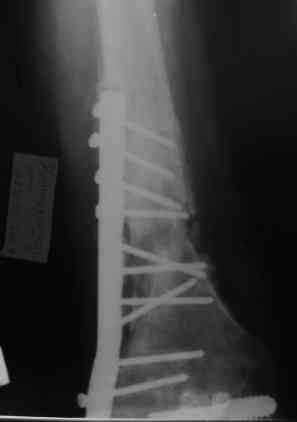

Уважаемые коллеги! Пациент лечился по поводу перелома н/3 бедра 1 год назад.

В настоящий момент: Несросшийся перелом н/3 правого бедра. Остеомиелит, свишевая форма.Контрактура коленного сустава.

Не факт, что поможет. Вариант классический в стране ГА Илизарова - санация - удаление всего мертвого с резекцией и потерей длины - аппарат для сращения и восстановления длины в один или два этапа (судя по ситуации). Многократно опробован. Тем паче, что остеомиелит хоть и травматический (операционный), но не канальный-тотальный (от штифта), а достаточно локален (от пластины).

Привет. Я имел в виду предложенную Вами программу лечения. Поражение кости остеомиелитическим процессом (судя по рентгенограммам) не канальное - когда спейсер можно поставить в канал после санации на какое-то время, а по всей окружности кости - когда придется делать спейсер в виде простой "болванки на арматуре). Вероятнее всего при хорошей санации получится дефект и укорочение. При втором этапе (как я понял, вы планируете БИОС) не факт, что восстановите длину и не "полыхнет" инфекция. Поэтому и предложена другая программа. Ваше право выбора - удачи на сложном пути избавления больного от ятрогенного о\миелита. Если проинформируете, что получилось, спасибо.